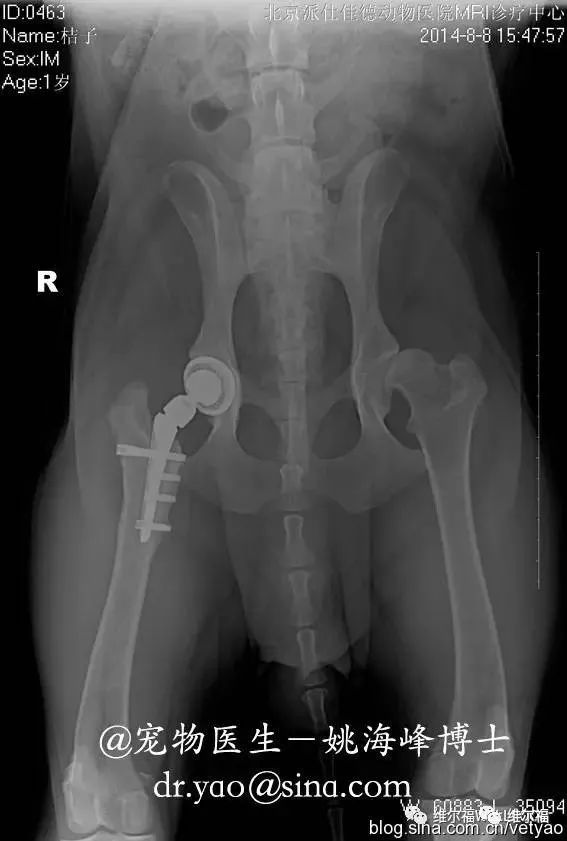

髋关节发育不良,是一种很常见的遗传疾病。简单地说,就是狗的大腿骨和骨盆连接的地方,全部或部分的离开了原本应该在的位置,就好比轴承偏移了位置,越用就会磨损的越厉害。从外观上看,会出现跛行、兔子跳等症状。这个疾病很难治愈,除非通过手术,切掉原有的髋关节和股骨头,更换一套新的连接系统。否则,狗每走一步路,就会产生一次疼痛,病痛将伴随它终生。

这个疾病疗效较好的治疗手段,是做髋关节置换术。姚海峰博士的微博里曾经多次详细介绍过该手术的方法。简单地说,就是锯掉发育不良的关节,使用一个人工的关节来替换: